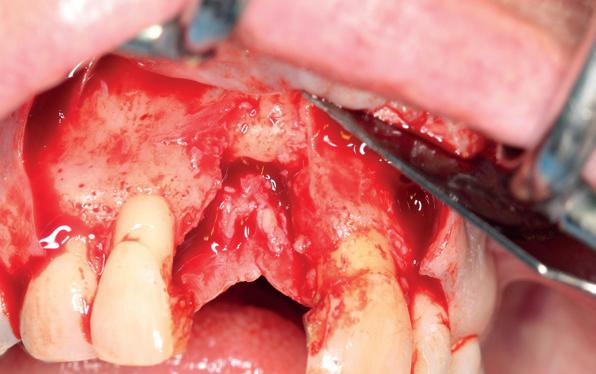

In het onderfront werd autoloog bot geoogst uit de kin regio ten behoeve van augmentatie (afbeelding

9. Botopbouw onderfront

9). In de bovenkaak werd bilateraal een sinuslift uitgevoerd. Aansluitend werden in beide kaakhelften implantaten geplaatst (afbeelding 10).